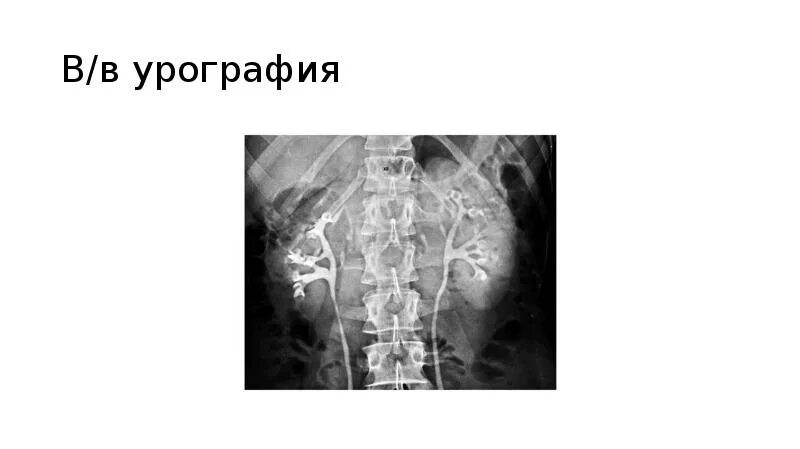

После урографии